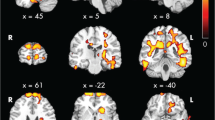

Regional associations between FA and neurocognitive functions with observed effects of CKD revealed a cluster of white matter tracts in the whole CKD group (complete MRI and neurocognitive data, n = 23), in which lower FA was associated with lower eFSIQ (Fig. 1). This cluster of tracts involves the SLF, CST, ATR, and IFOF. No regional associations between FA and processing speed and working memory were observed. The cluster of white matter tracts relating to eFSIQ in CKD patients was selected for further analyses investigating the relation between brain structure and neurocognitive functioning.

Regional associations between FA in cluster affected by CKD and eFSIQ using threshold-free cluster enhancement correction in TBSS, showing a significant positive correlation between eFSIQ and white matter integrity in CKD patients (displayed in red–yellow, n = 23, sociodemographic characteristics were included in the model as covariates). Image is illustrated the following coordinates: (x = 26, y = − 7, z = 20) and shows the whole brain skeleton (at FA > 0.3, in green), overlaid on standard MNI 152 1-mm T1 brain. Significant group differences are “thickened” towards the full width of the white matter tract to increase visualization. The scatterplot shows the association between eFSIQ and FA in the cluster that is associated with eFSIQ in the CKD sample. Abbreviations: FA, fractional anisotropy; L, left